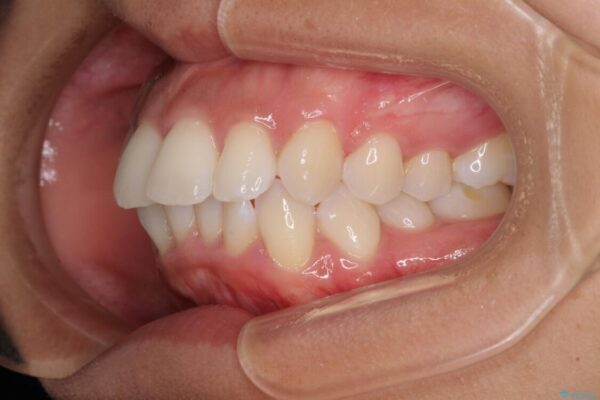

治療後

• 抜歯矯正で唇を閉じやすく 目立たないワイヤー装置 治療後画像

治療後について

抜歯スペースに前歯を移動させることで歯の突出感が改善され、非常に唇が閉じやすい仕上がりとなりました。